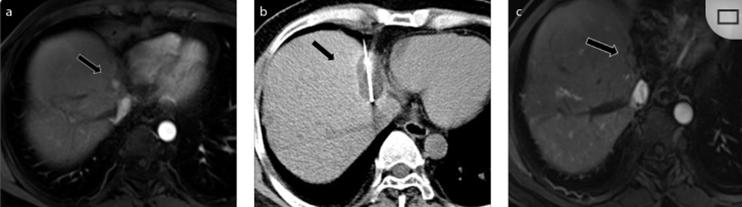

62歲女性,肝轉(zhuǎn)移(卵巢癌)腫瘤的完全消融病例(a)軸向CT顯示病變位置毗鄰心臟和上腔靜脈(黑色箭頭)。(b)術(shù)中軸向CT掃描:使用三個(gè)冷凍探針。1個(gè)月后的軸向(e)和冠狀位(f)增強(qiáng)CT掃描顯示低密度區(qū)域,由于肉芽組織反應(yīng)引起的邊緣增強(qiáng)。

技術(shù)成功100%,92% 的病灶中觀察到腫瘤完全消融。16 名患者 (33%) 出現(xiàn)局部復(fù)發(fā)。10 名患者 (20%) 因局部復(fù)發(fā)或腫瘤消融不完全而接受二次冷凍消融術(shù)。

7名患者出現(xiàn)輕微并發(fā)癥,未發(fā)現(xiàn)膿腫形成、膽漏、膽汁瘤或血液學(xué)變化。冷凍消融可安全、有效治療毗鄰重要臟器的原發(fā)性肝臟腫瘤和肝轉(zhuǎn)移瘤患者,有效控制腫瘤局部進(jìn)展,使患者生存獲益。我國(guó)作為肝癌大國(guó),對(duì)于肝癌的治療一直給予高度重視?;趯<夜沧R(shí)和相關(guān)文獻(xiàn)研究結(jié)果顯示,冷凍消融技術(shù)具有高效、低成本、創(chuàng)傷小、適應(yīng)證廣、并發(fā)癥相對(duì)較少等優(yōu)點(diǎn),可有效延長(zhǎng)患者生存期、提高生活質(zhì)量、降低患者經(jīng)濟(jì)負(fù)擔(dān)。因此,冷凍消融技術(shù)在肝癌的應(yīng)用中有著極高的潛力和廣泛的發(fā)展空間。